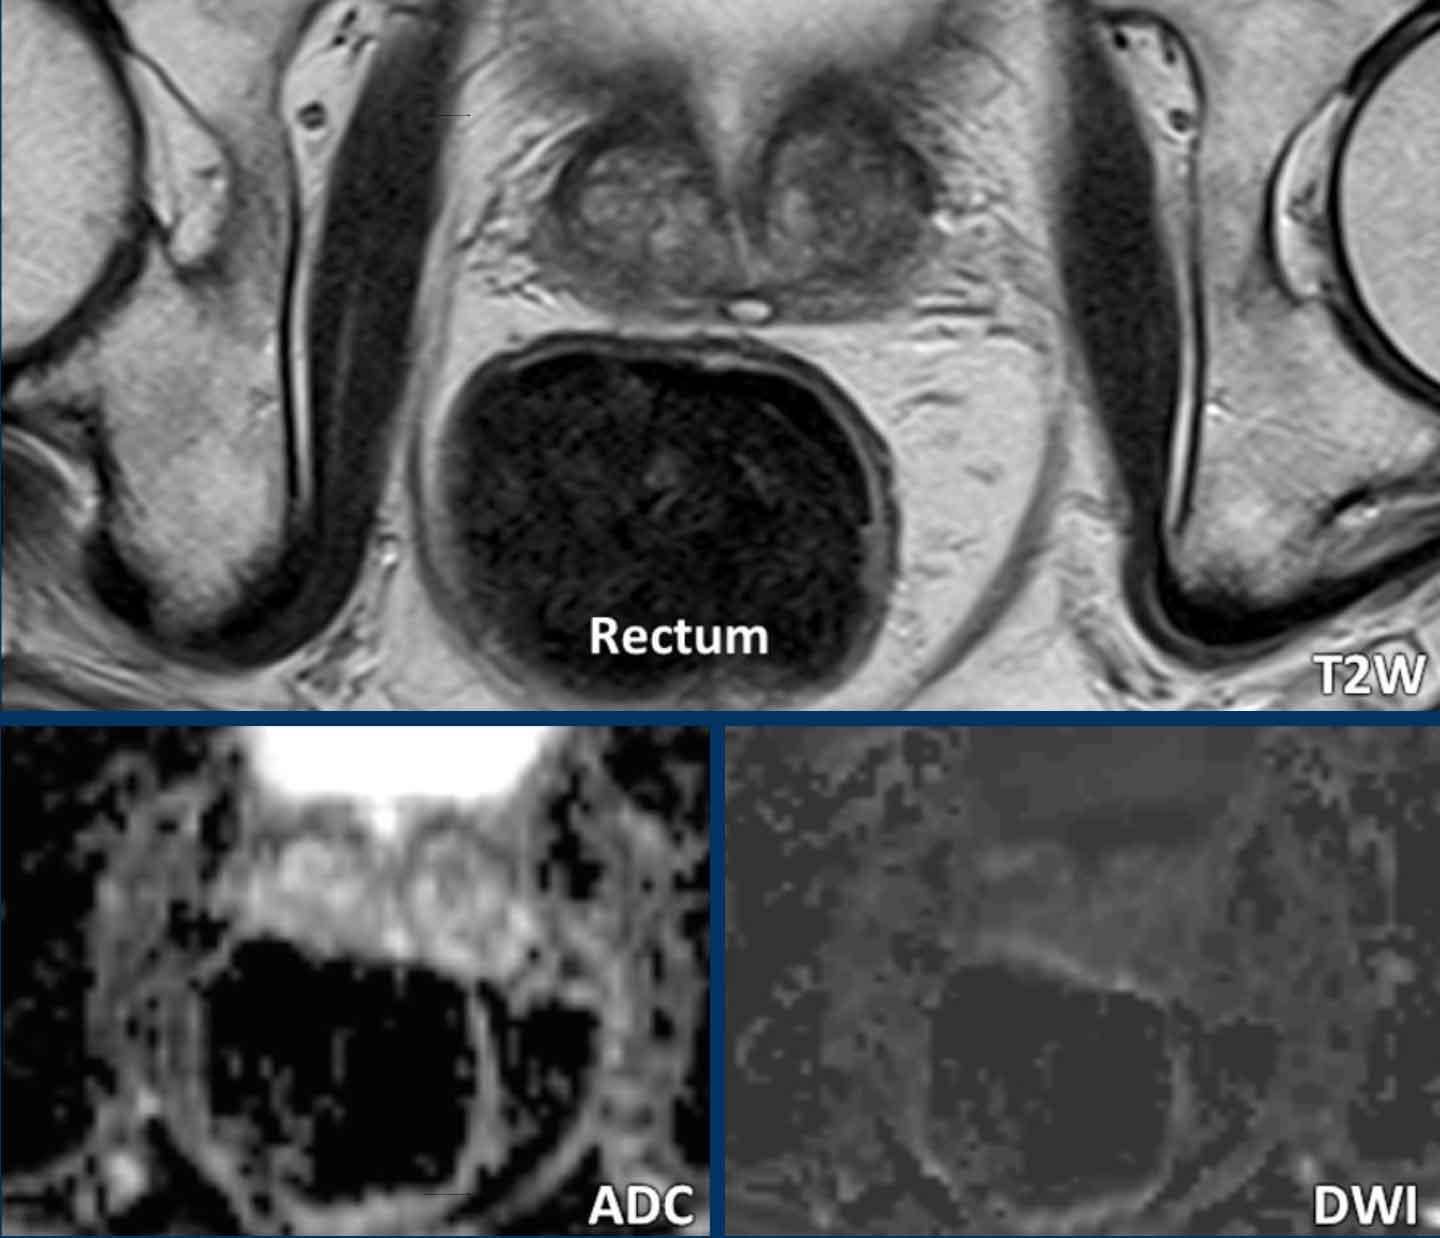

Thuốc giảm co thắt

Có thể cân nhắc sử dụng thuốc giảm co thắt trước khi thực hiện thủ thuật nhằm giảm thiểu chuyển động của ruột non và ruột già.

Khí và phân trong trực tràng có thể làm giảm chất lượng đánh giá khuếch tán.

Các hình ảnh này thuộc về một bệnh nhân không được chuẩn bị gì trước khi chụp MRI.

Sự hiện diện của khí và phân trong trực tràng gây ra xảo ảnh biến dạng tuyến tính rời rạc tại vùng tuyến tiền liệt, làm hạn chế độ chính xác chẩn đoán của cả chuỗi DWI và ADC.

Đây là ví dụ về một bệnh nhân đã được thụt tháo chuẩn bị tối thiểu vài giờ trước khi chụp.

Kết quả là trực tràng được làm sạch hoàn toàn. Mặc dù thụt tháo có thể gây nhu động trực tràng, nhưng không quan sát thấy xảo ảnh nào ở bệnh nhân này.